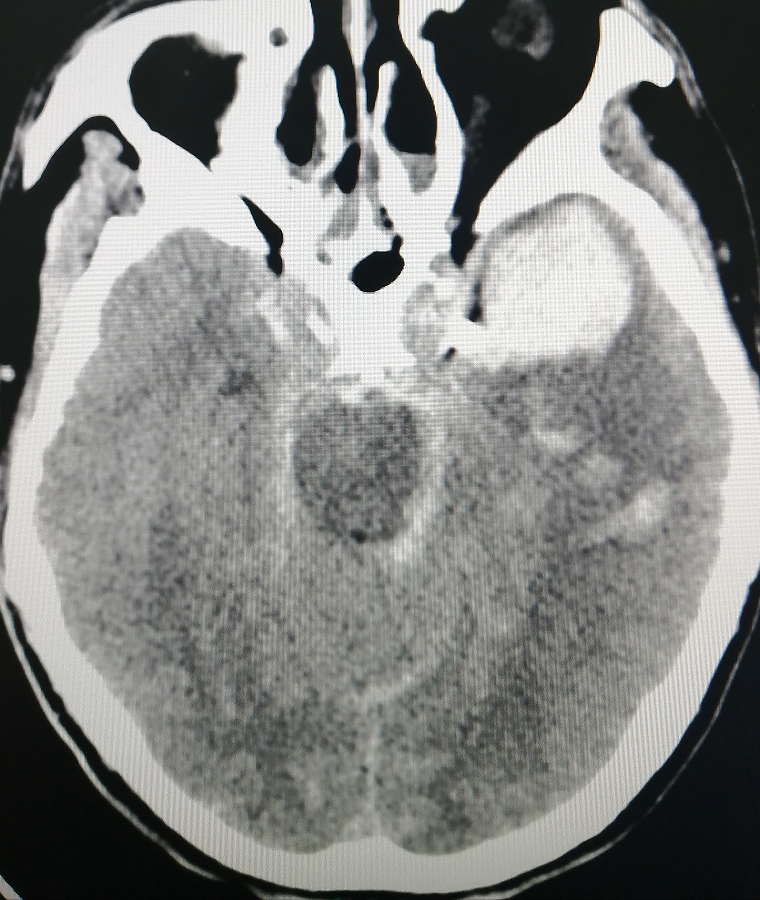

70岁的患者王某被家人发现时已经头痛、意识不清3小时了,既往有脑梗死多年,被家人紧急送往医院。神经外科医生董永军接诊患者并完善相关检查后,初步诊断为自发性蛛网膜下腔、左侧颈内动脉C6端动脉瘤(破裂)、吸入性肺炎和高血压病3级。

神经外科团队在北医三院驻延专家陈晓东教授和主任田德洲的带领下,由董永军副主任,张晨主治医生行颅内动脉瘤介入栓塞治疗。结合造影检查结果,考虑左侧C6段破裂动脉瘤,5mm×7.6mm,瘤径约5.7mm,可见子瘤形成。胚胎型后交通动脉。拟行经皮股动脉穿刺多微导管弹簧圈栓塞术。结合造影结果,考虑左侧C6段破裂动脉瘤,5mm×7.6mm,瘤径约5.7mm,可见子瘤形成。胚胎型后交通动脉。最终为患者王某实施了行经皮股动脉穿刺多微导管弹簧圈栓塞术。王某目前恢复良好,已顺利出院。